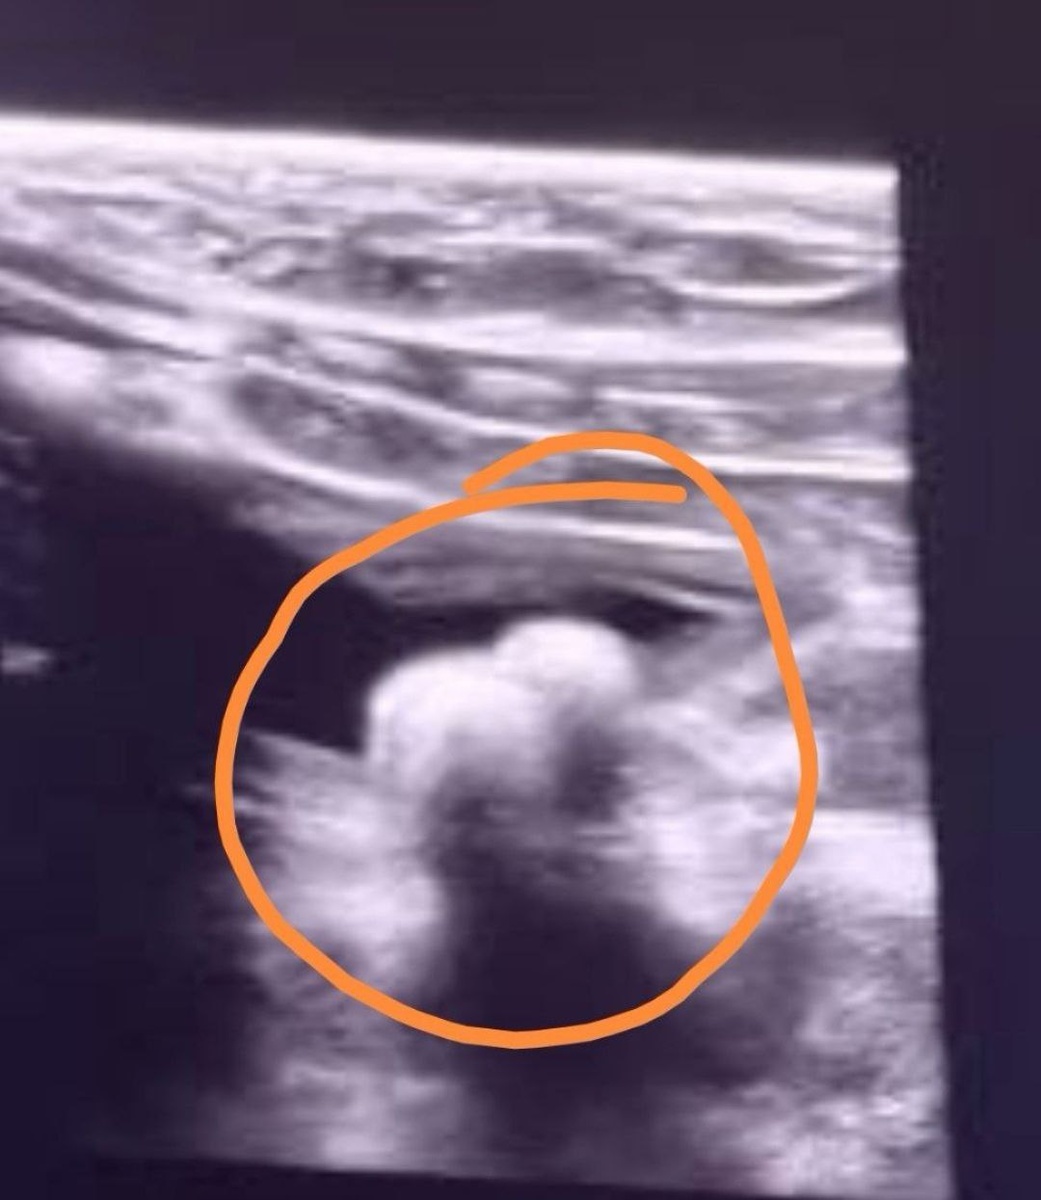

Наша страдалица кошечка Софочка прооперирована🙏🙏. Удалили два камешка из мочевого, которые её очень мучили последнее время Проблемы со здоровьем у малышки давно уже, несколько лет, но все это время камней таких не было конечно. В марте на УЗИ все было вообще хорошо, даже песочка не нашли, поставили идиопатический цистит, а вот сейчас уже аж до операции дело дошло😔. Врач сказала, что такой организм у нее и не исключает, что камни могут появиться вновь, поэтому на спец корме скорее всего Софочка будет пожизненно и на определённых медикаментах. Ну посмотрим, что покажет анализ. Один из двух камней отправили на анализ для определения структуры и вида, чтобы в дальнейшем выбрать правильный корм и тактику поддержания здоровья Софочки. После операции кошечка чувствует себя очень даже неплохо, шовчик заживает, 22 числа повезём её на приём🙏. Операция проведена в долг, за что врачам огромное спасибо за доверие и возможность лечить, но его нужно опять закрыть, поэтому в очередной раз очень

Наша страдалица кошечка Софочка прооперирована🙏🙏. Удалили два камешка из мочевого, которые её очень мучили последнее время

Проблемы со здоровьем у малышки давно уже, несколько лет, но все это время камней таких не было конечно. В марте на УЗИ все было вообще хорошо, даже песочка не нашли, поставили идиопатический цистит, а вот сейчас уже аж до операции дело дошло😔. Врач сказала, что такой организм у нее и не исключает, что камни могут появиться вновь, поэтому на спец корме скорее всего Софочка будет пожизненно и на определённых медикаментах. Ну посмотрим, что покажет анализ.